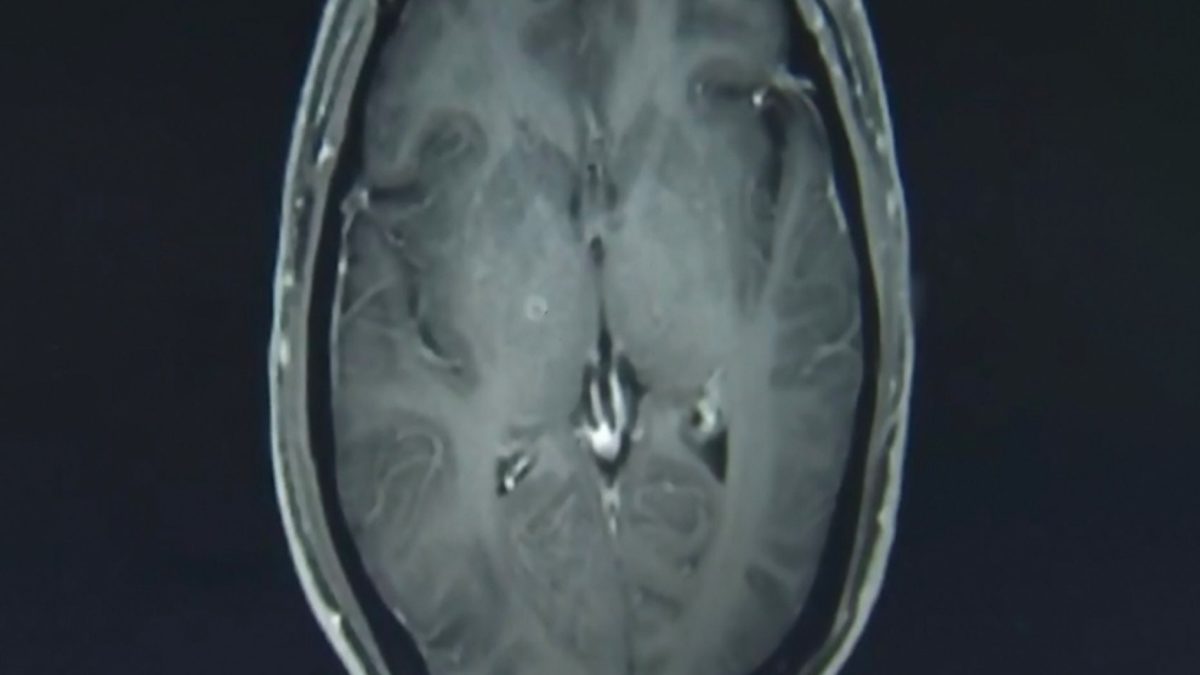

Τα σκουλήκια παράσιτα, που βλέπετε εδώ σε τομογραφία του εγκεφάλου του 43χρονου, εισήλθαν στο σώμα του μέσω του πεπτικού συστήματος, αφότου κατανάλωσε μη επαρκώς μαγειρεμένο χοιρινό κρέας.

Ο δρ. Jianrong εξήγησε ότι οι προνύμφες εισήλθαν στο σώμα του Zhongfa μέσω του πεπτικού συστήματος και ταξίδεψαν προς τα πάνω μέσα από την κυκλοφορία του αίματος. Διαγνώστηκε επισήμως με κυστικέρκωση (cysticercosis) και νευροκυστίτιδα (neurocysticercosis) και έλαβε αντιπαρασιτικό φάρμακο και άλλα φάρμακα για την προστασία των οργάνων του από περαιτέρω βλάβες.